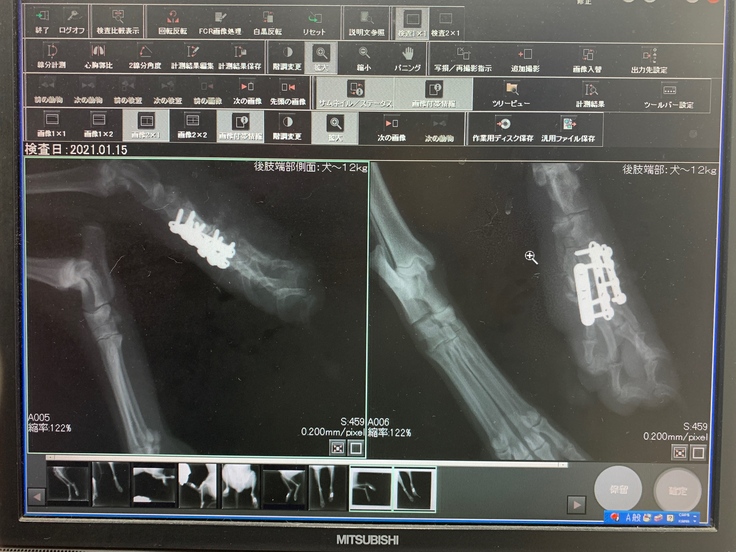

モモの左後ろ脚、人間の手首から手の甲にあたる部分の骨が粉々に砕けていたため、長時間に及ぶ複雑な手術になりました。

今でも金属のプレートが入っています。